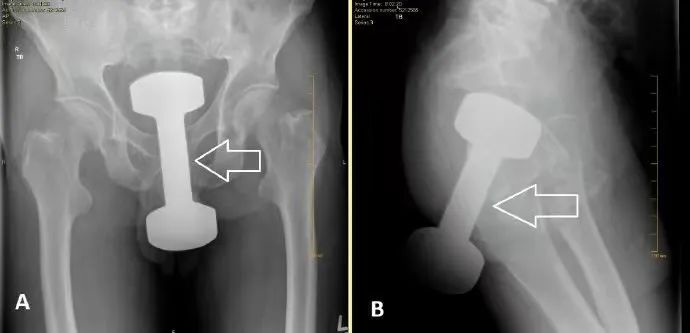

哑铃